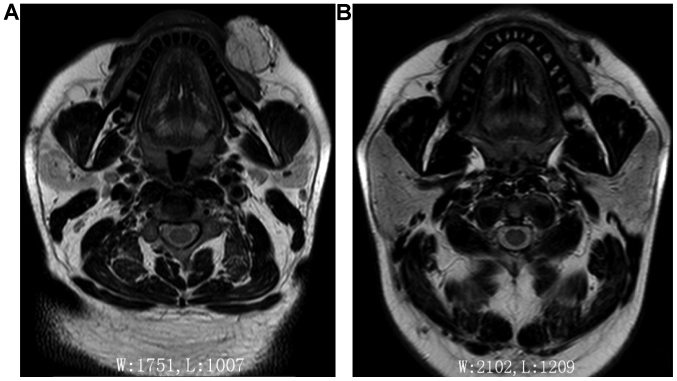

The curative effects of the two groups are shown in Table II. In the treatment group the treatment times were significantly less than those of the control group (P<0.05). The results of MRI examinations were compared before treatment and 8 weeks after the last treatment to obtain the final efficacy. It was found that the effective rate of the treatment group was significantly better than the control group (P<0.05). Figs. 1–3 show typical cases.

Figure 2.

Comparison between pre-treatment (A) and post-treatment (B) MRI scan in patient with venous malformation of the left facial region.